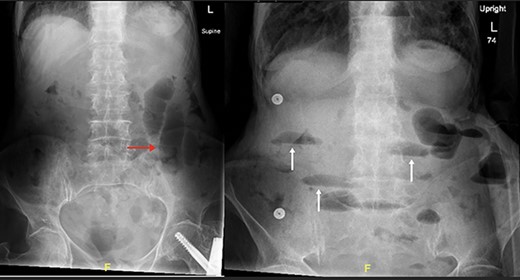

Supine and erect abdominal radiograph demonstrate distended small bowel loops (red arrow) with multiple air fluid levels (white arrow) suggesting small bowel obstruction.

The patient’s lab results revealed leukocytosis of (12.40 m/mm3), and C-reactive protein of (28 mg/l). Abdominal X-ray demonstrated distended small bowel loops with multiple air fluid levels (Fig. 1). Moreover, CT revealed right sided obturator foramen hernia containing a segment of distal ileum causing high-grade small bowel obstruction, which reached up to 4 cm (Fig. 2). The CT also showed extensive bronchiectasis and consolidation with mucus plugging in the lung base.